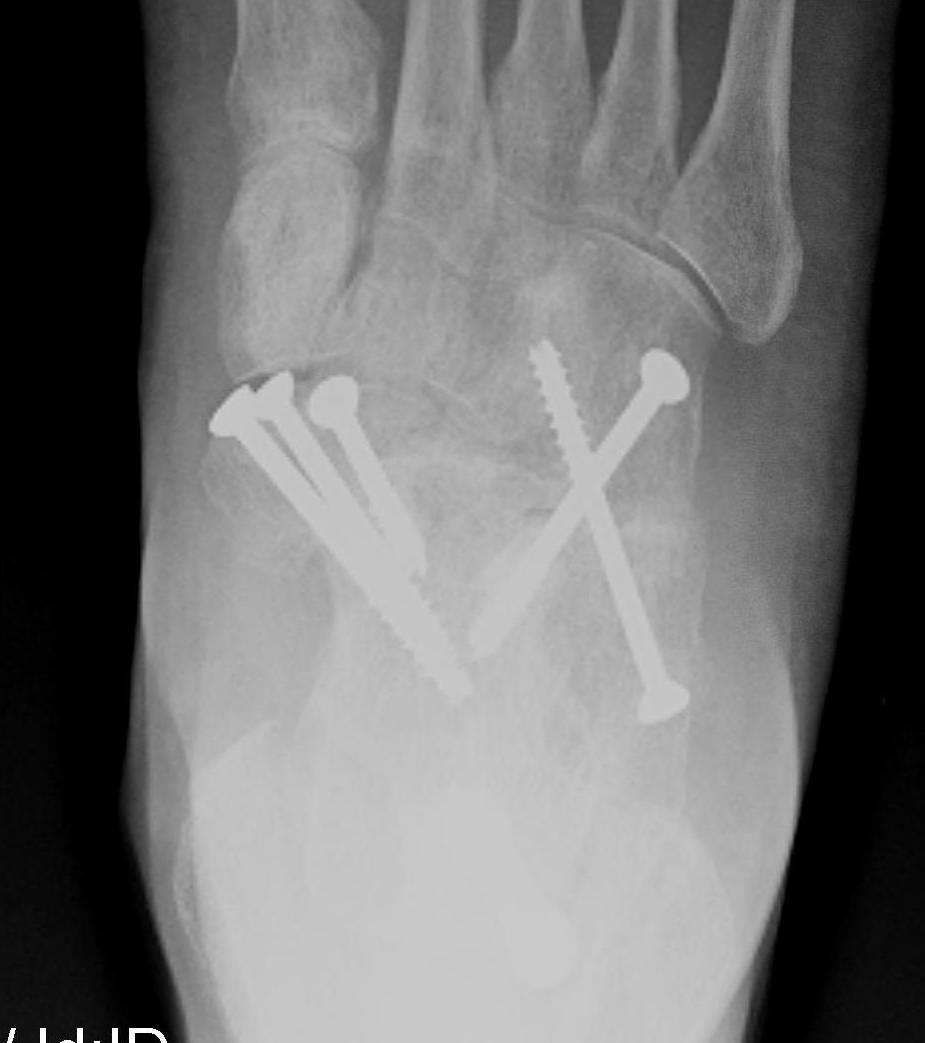

Fixation

- 6.5 mm/ 8.0 mm cannulated screw

- inferior calcaneum into body and neck of talus / talus to calcaneum

- TJN screws

- CCJ screws +/- plate

- STJ screws